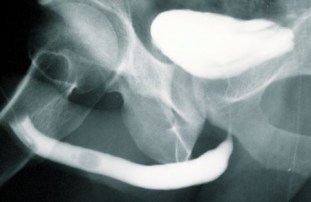

Estenosis de Uretra Anterior